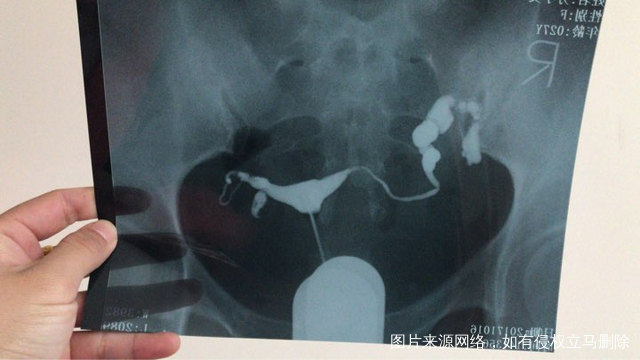

输卵管左侧通而不畅,右侧有积水可能